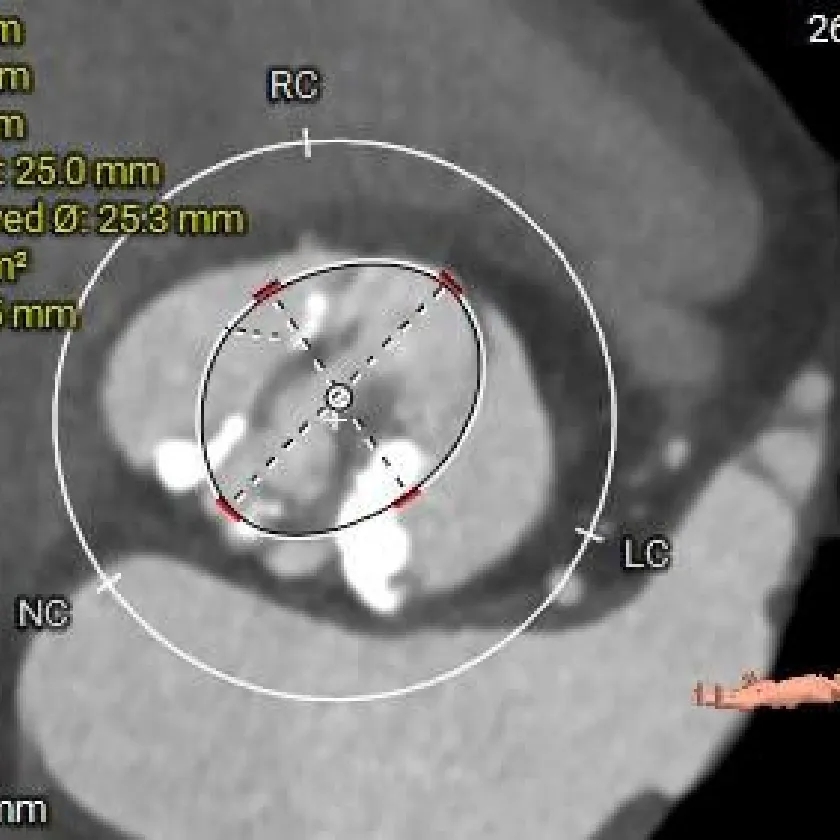

瓣上6mm

25.3mm